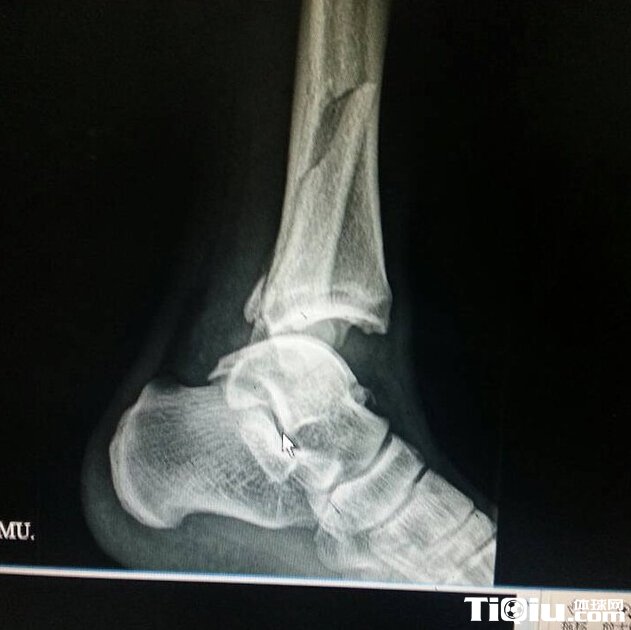

前国安悍将韧带骨头全断(/)